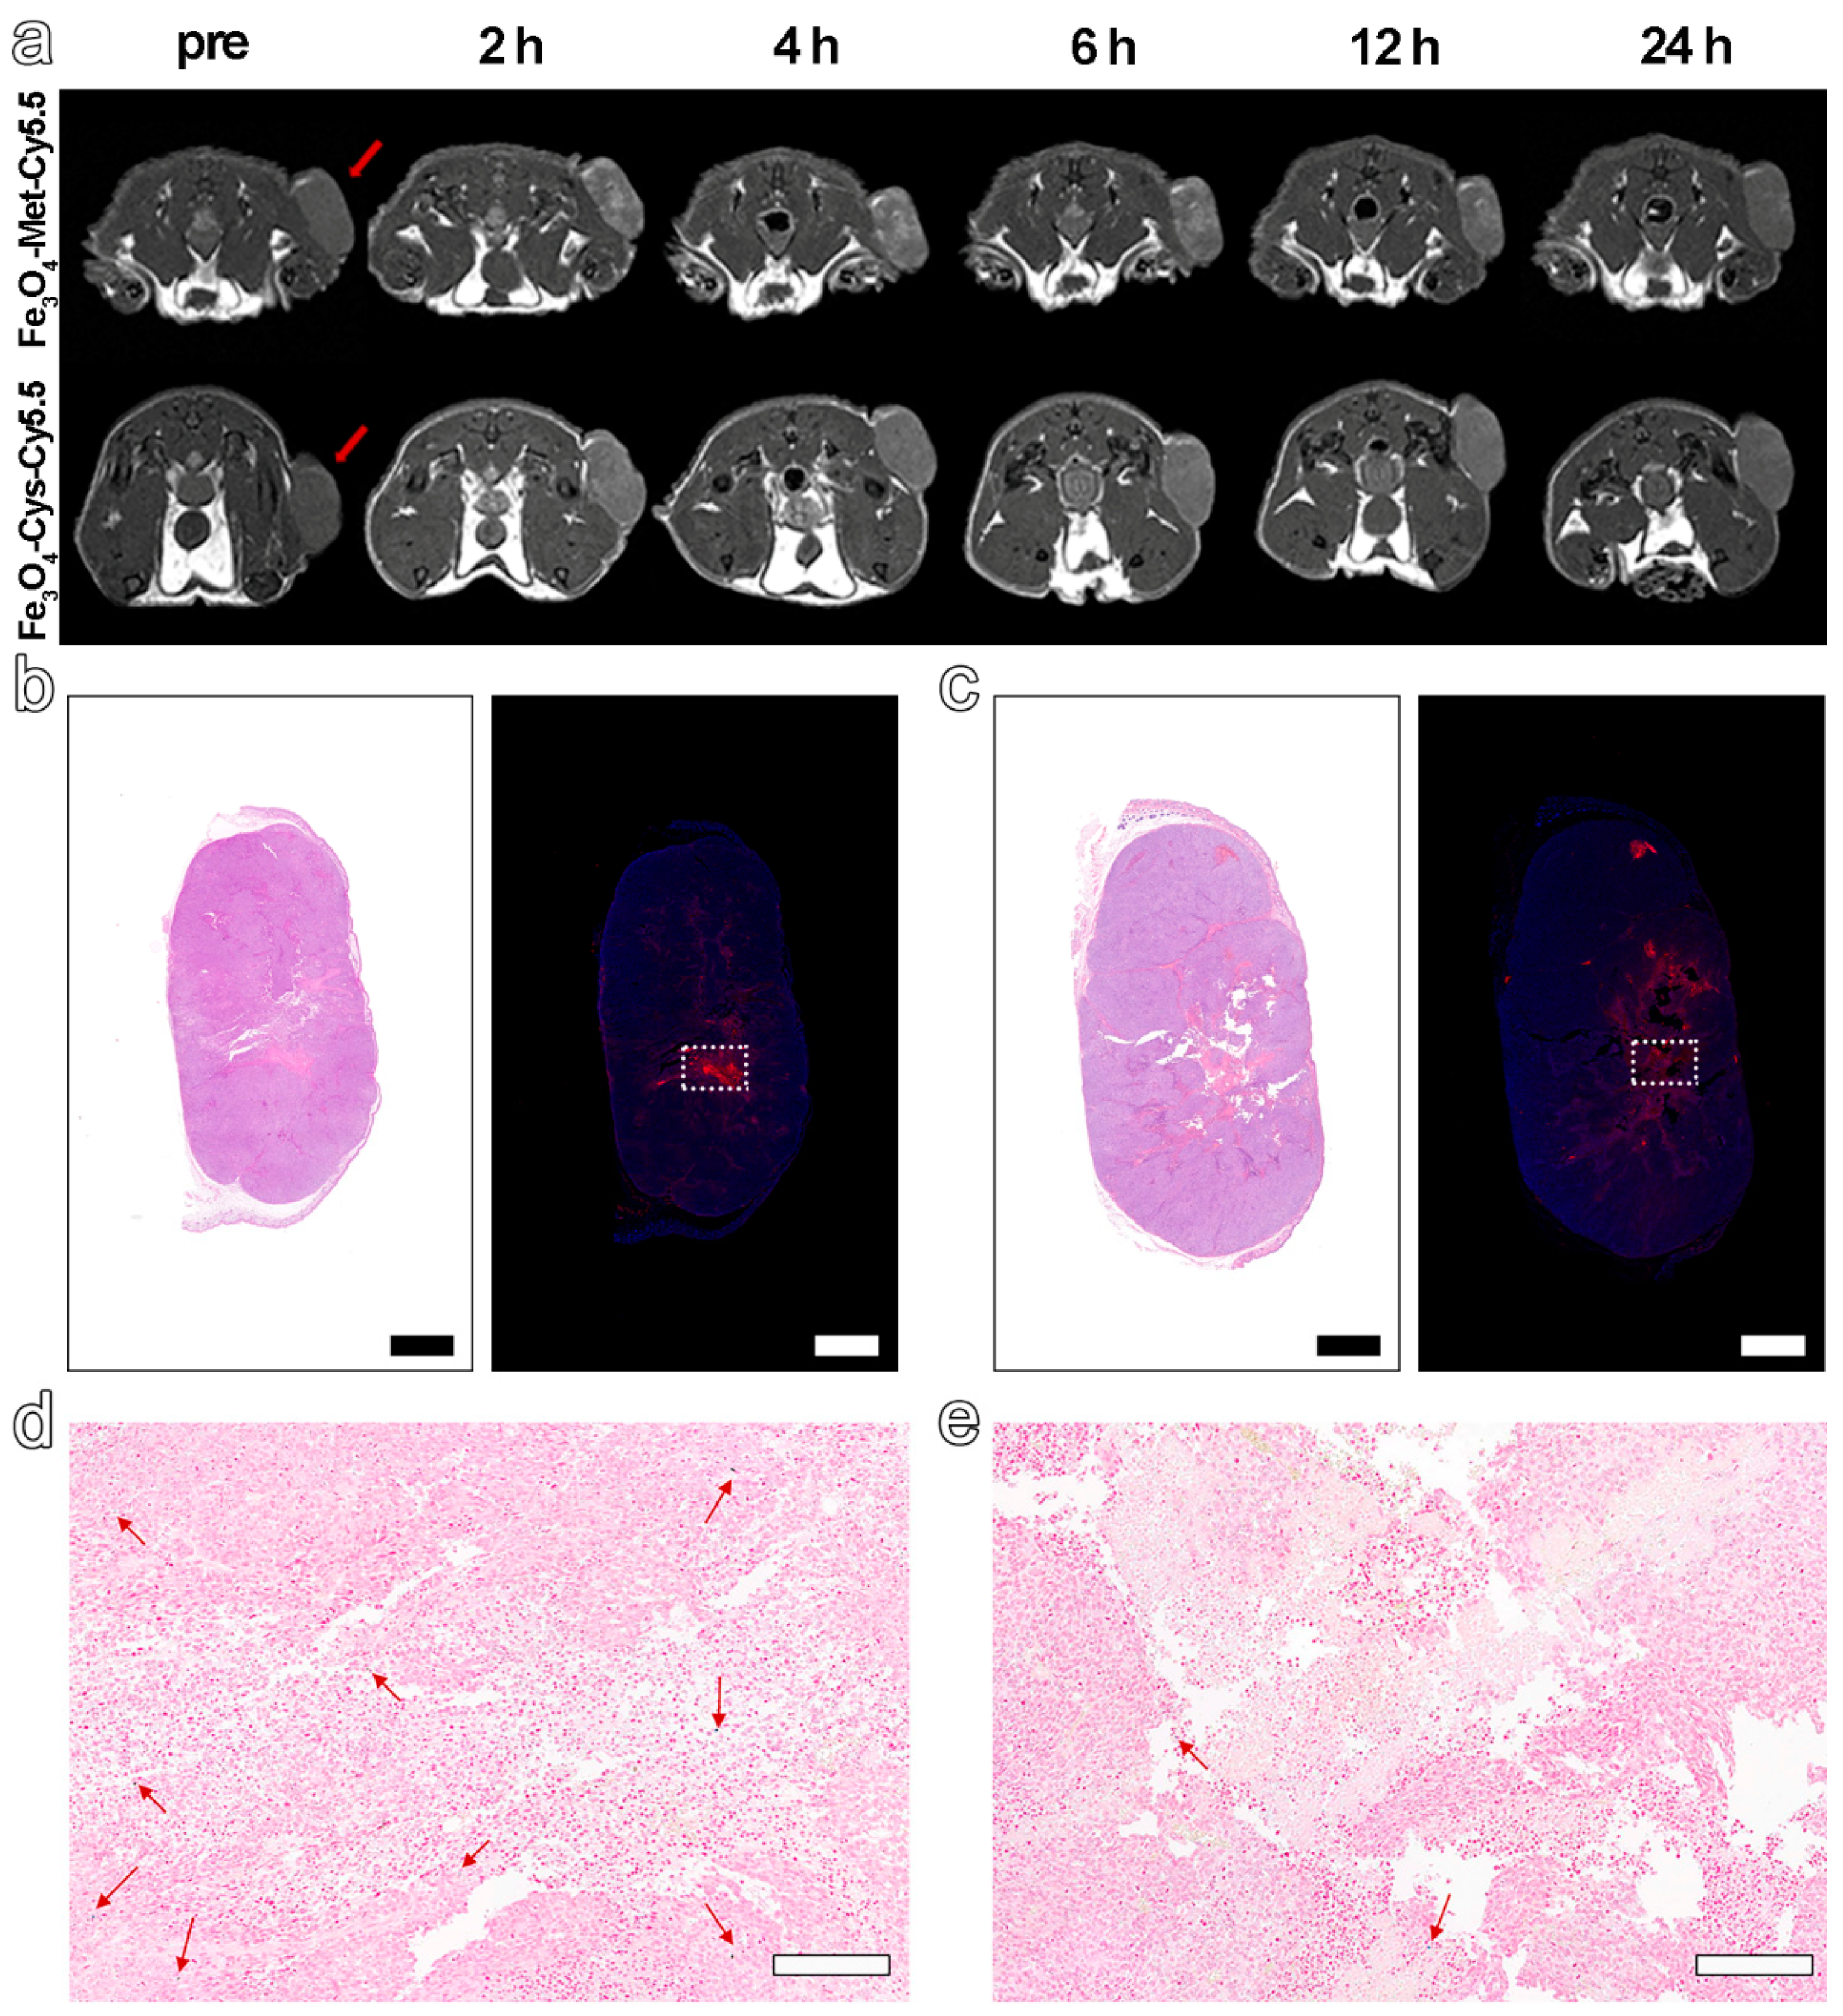

3.4. In Vivo T1-Weighted MRI of Tumors